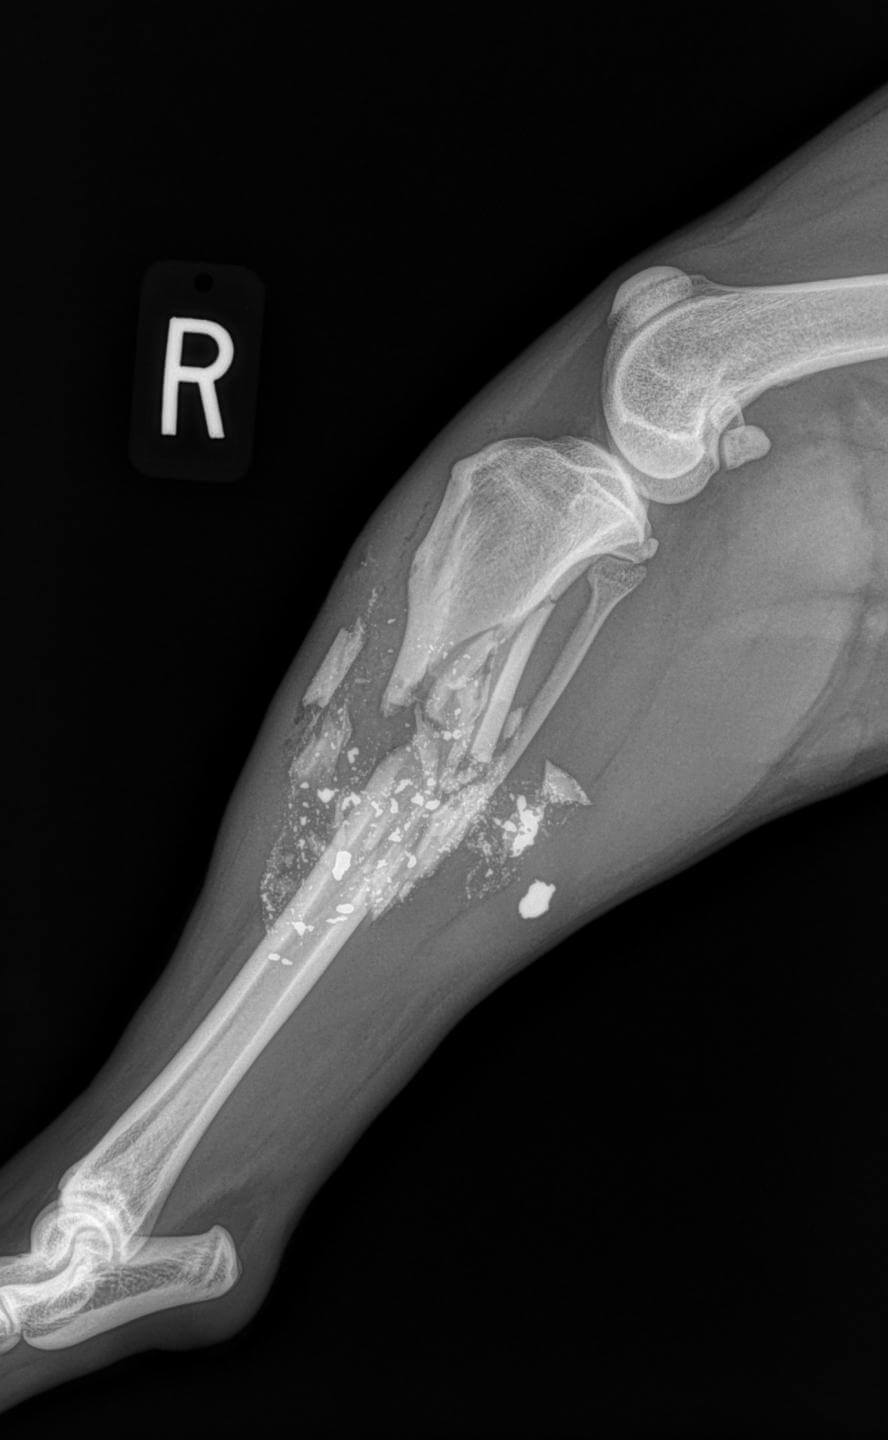

From buyxraysonline.com

FRACTURED LEGDOG Symptoms Of Fracture In Dogs Leg Find out how to care for your dog's leg injury. learn the signs of a broken leg in dogs, such as swelling, bruising, whining, and limping. Identifying a dog's broken bone can be challenging, but common signs include: learn the signs of a broken or dislocated leg in dogs, such as limping, swelling, pain, and difficulty moving. There. Symptoms Of Fracture In Dogs Leg.